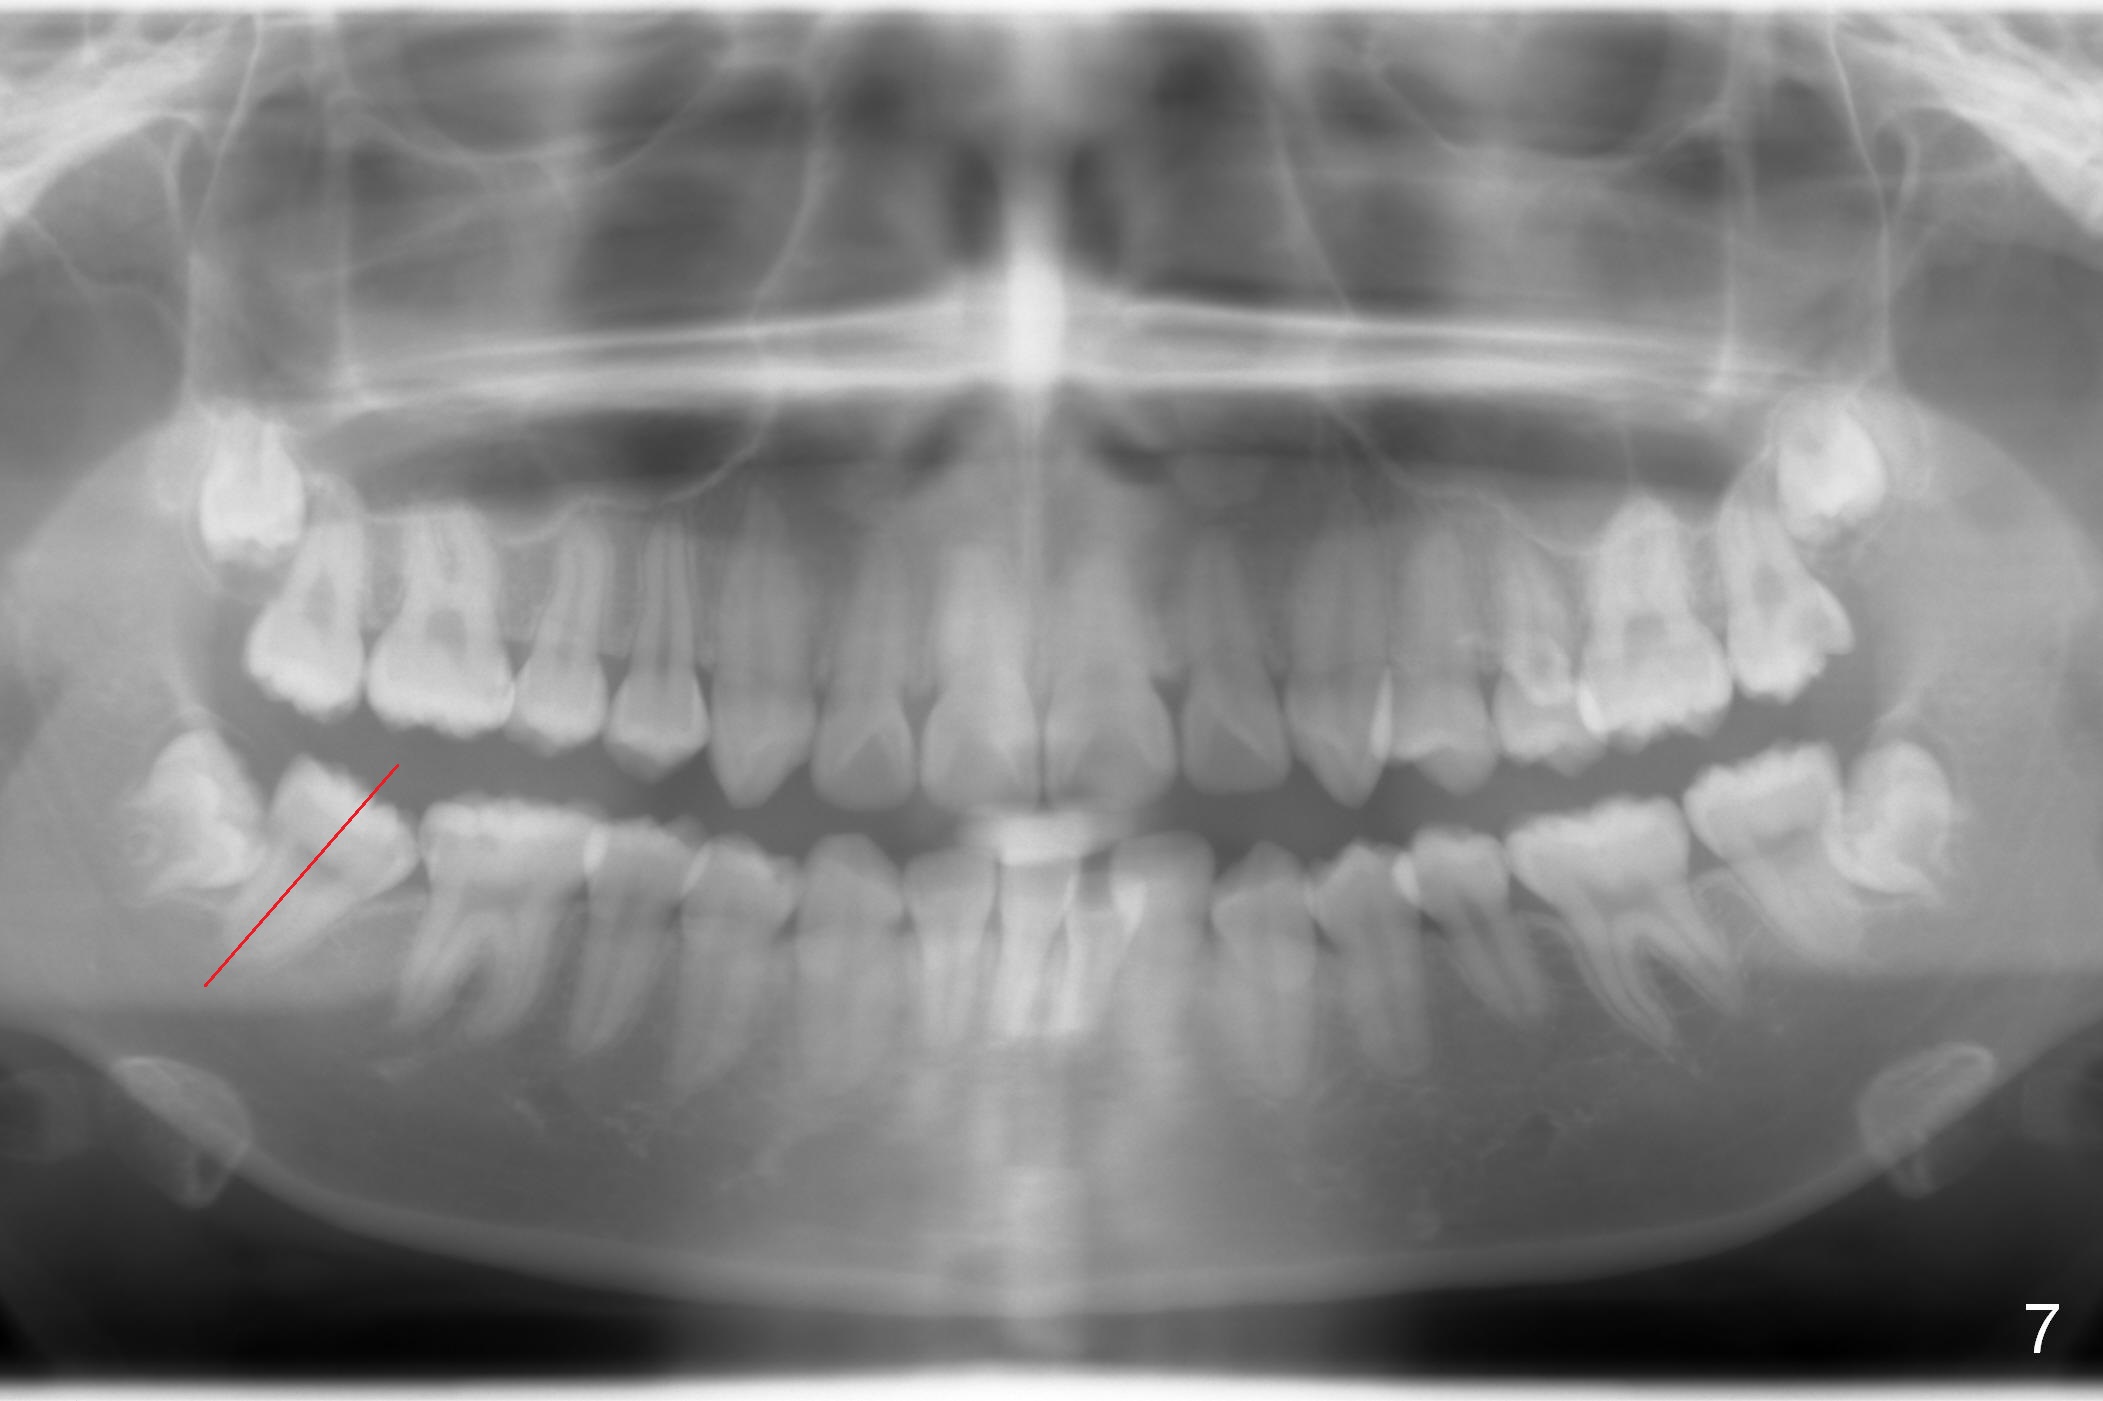

A 17-year-old woman will return for bracketing after caries control and deciduous tooth (Fig.6 arrowheads) extraction. Her profile is slightly protrusive (Fig.1,2). Crowding is more severe in the left posterior region (Fig.4) than the right one (Fig.3). The anterior crowding is also severe (Fig.5). Proximal reduction and use of power chain for constriction will be used instead of extraction of 4 bicuspids. Third molar extraction may have to be done prior to banding, especially for the lower right 2nd molar (Fig.7).

By looking at preop models (Fig.8-13), do you think whether extraction is a better option than non-extraction? Class II occlusion on the right (Fig.8), Class I on the left (Fig.10). With extraction of the 1st bicuspids, the posterior occlusion could be normal with further anterior protrusion (Fig.11). The upper arch is rounded (Fig.12); without extraction, the arch may turn out to be U-shaped. The lower arch is more crowded (Fig.13). Without space, the lower right 2nd molar may not be uprighted (Fig.7).